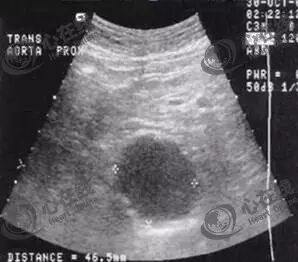

(2)腹部超声

腹部超声是一种无创检查方法,费用较低,但不能显示肾动脉以上结构,且易受肠气影响,准确性稍差。